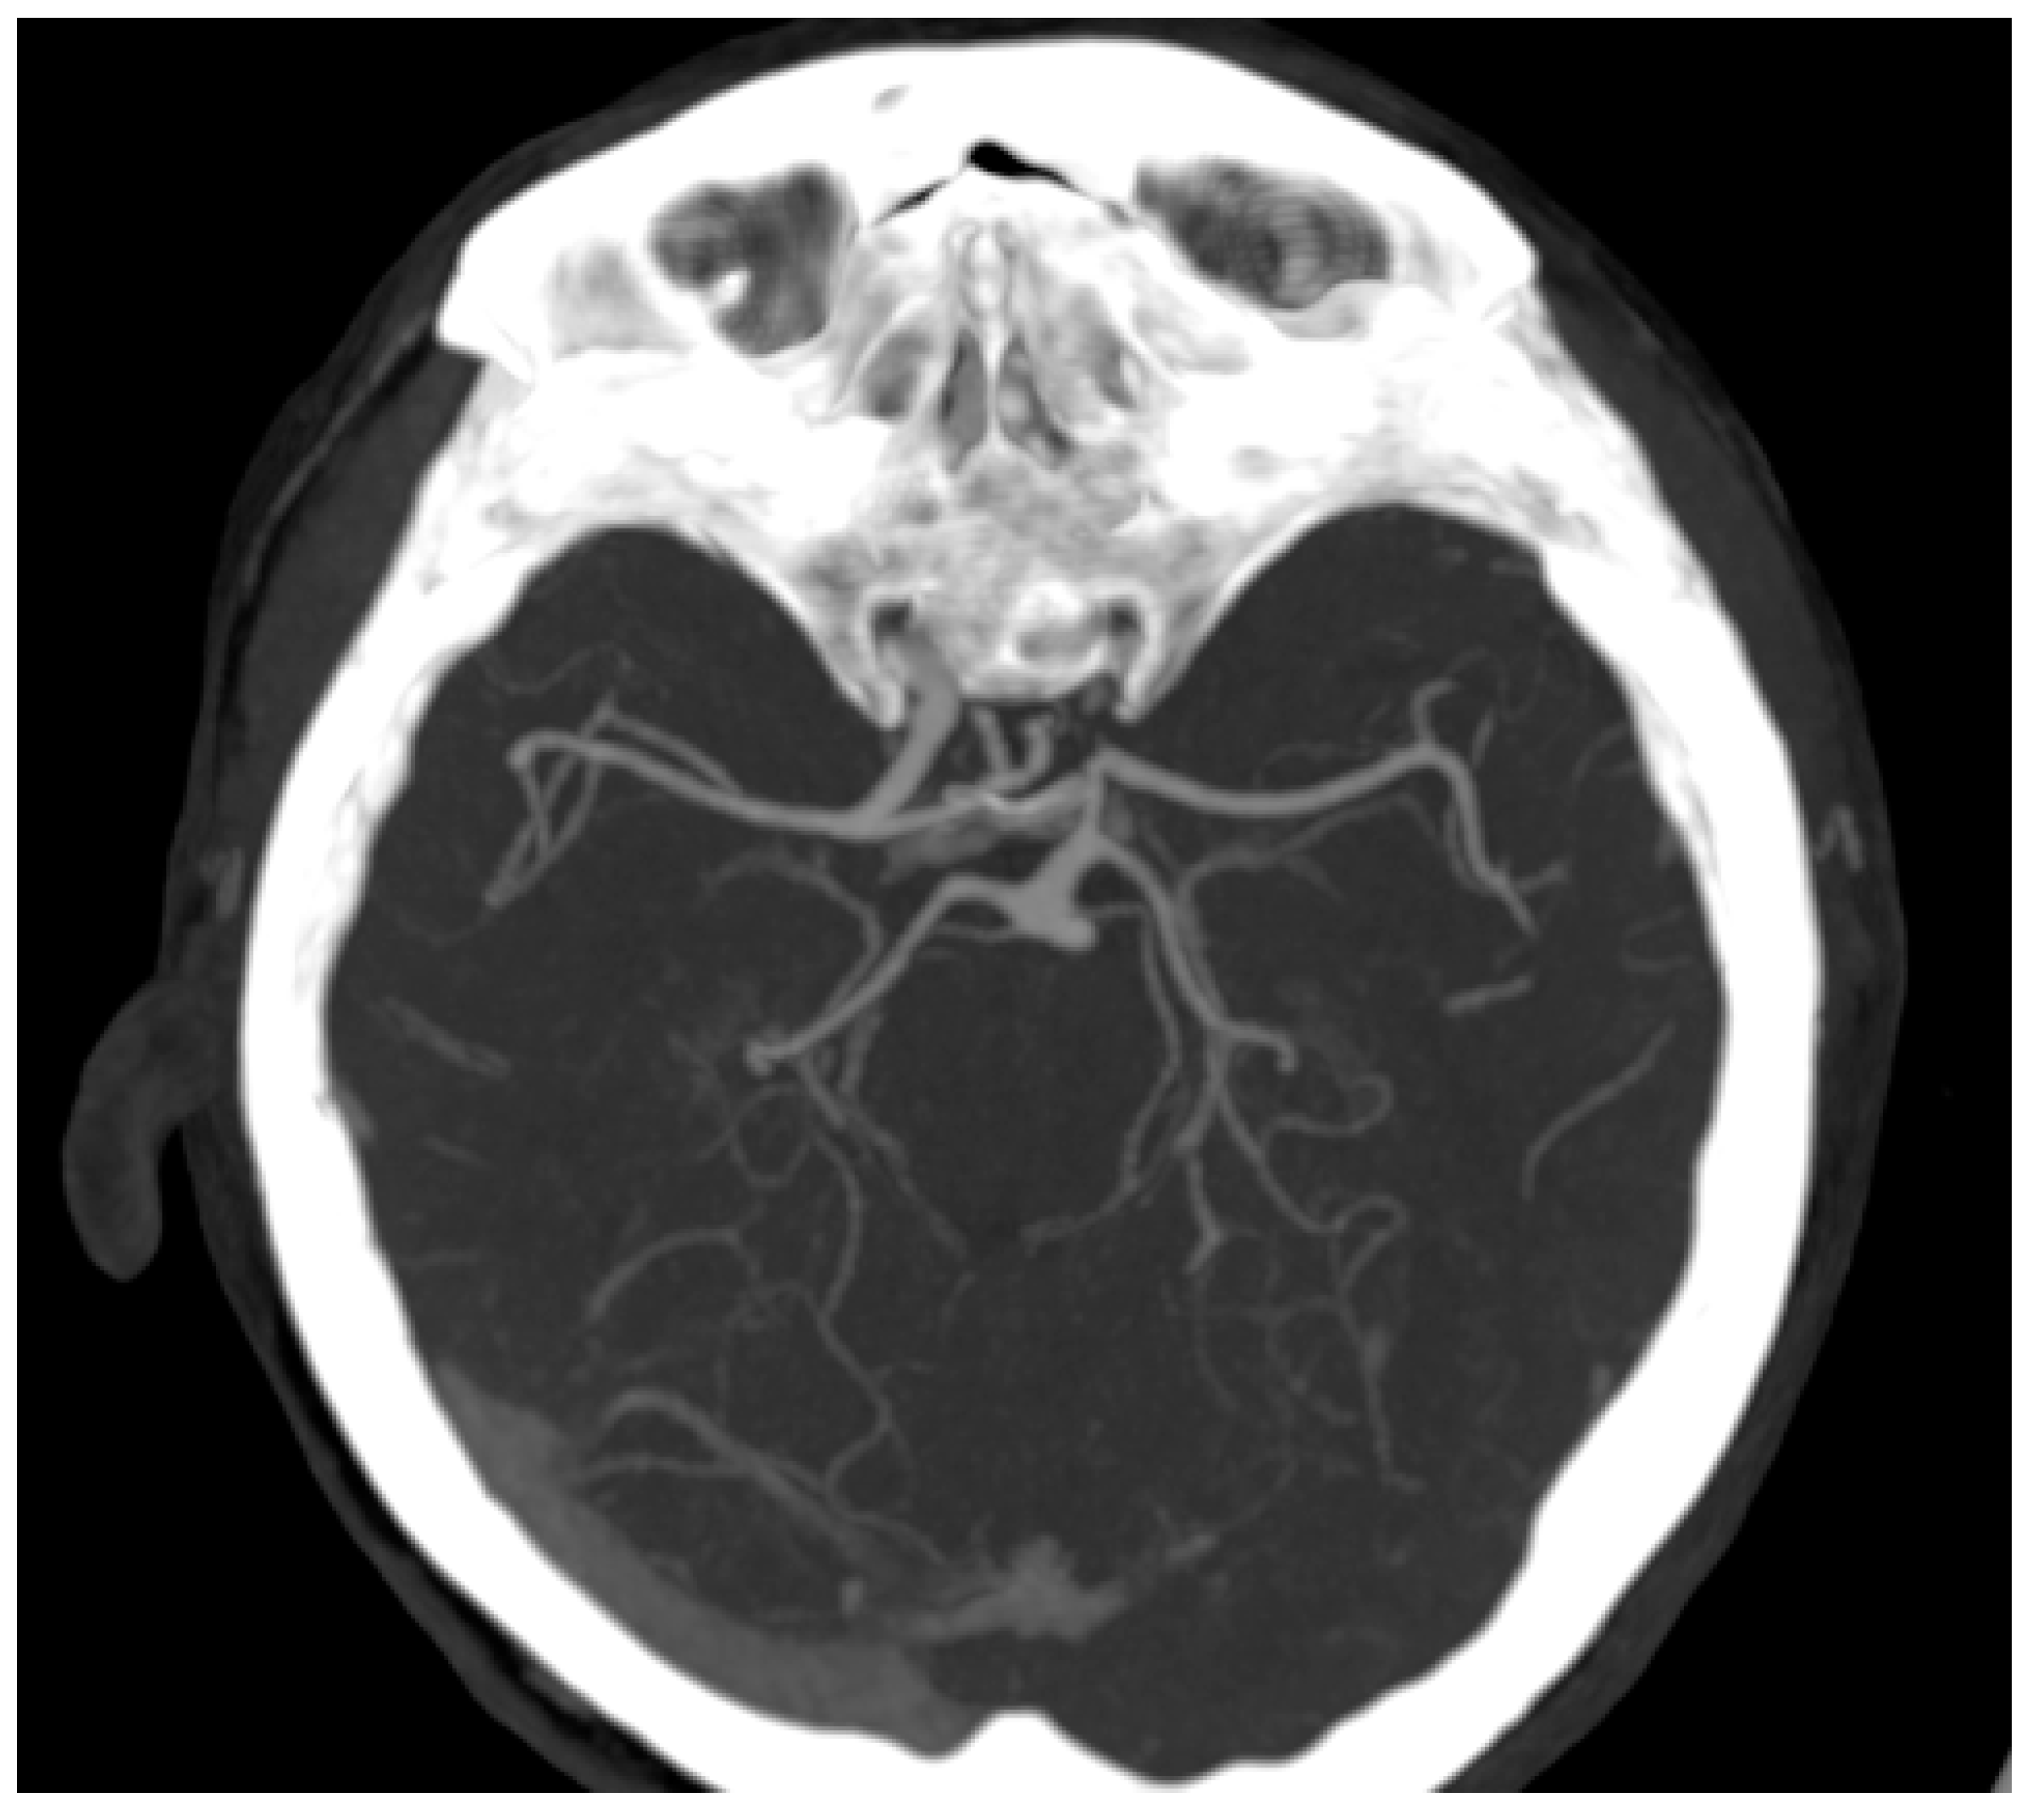

2. Case Report